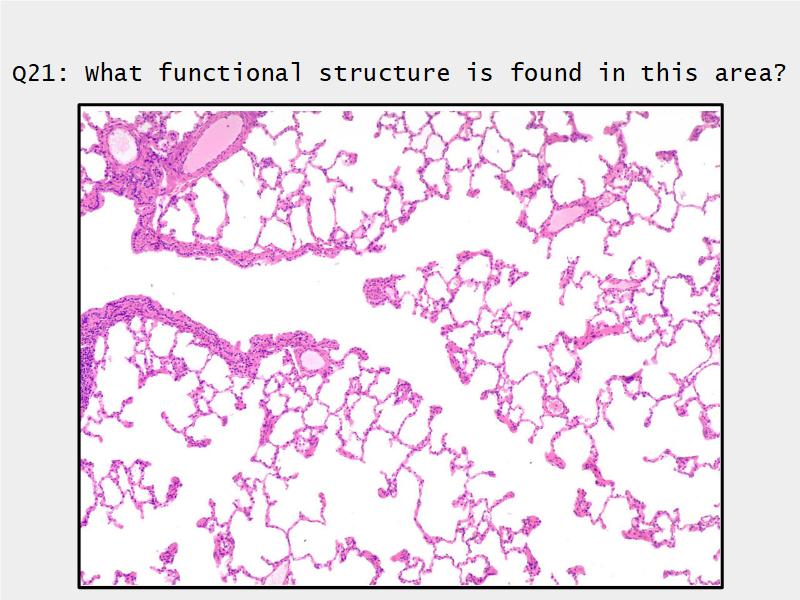

Respiratory Epithelium: Trachea